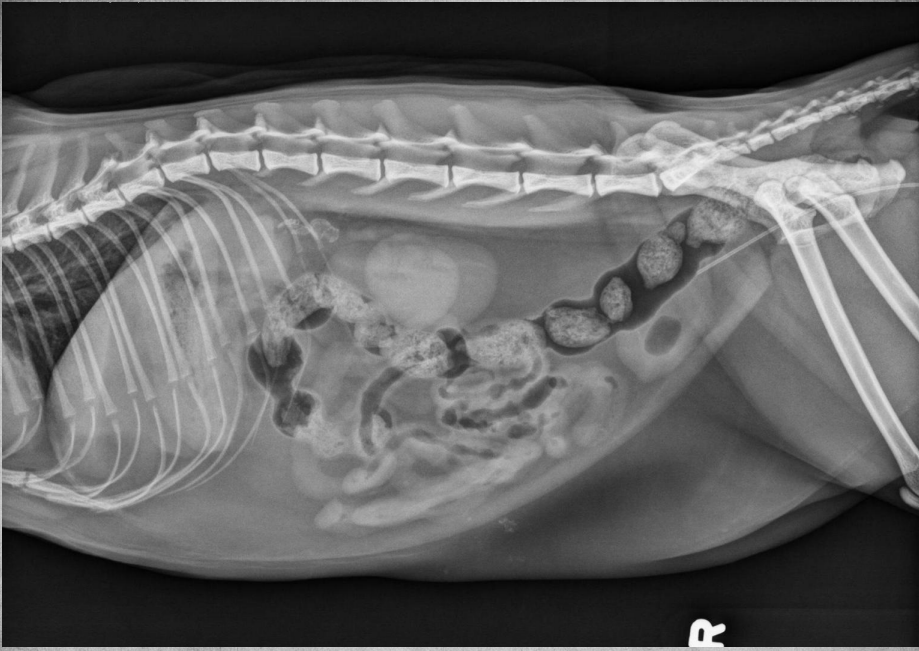

●6 mo female Great Dane

●Vomiting, loss of appetite for 3 days

●Suspected foreign body

● Entire small intestine moderately homogenously fluid filled, teeny bubbles throughout GI tract indicating GI hypomotility.

● Markedly gas-distended intestinal segment in mid-abdomen, reverse C-shaped, most likely normal caecum.

● Diffusedly fluid filled GIT with interspersed gas bubbles is most consistent with functional ileus from severe enteritis.

● No radiographically evident foreign body.

● Dx: Parvoviral enteritis